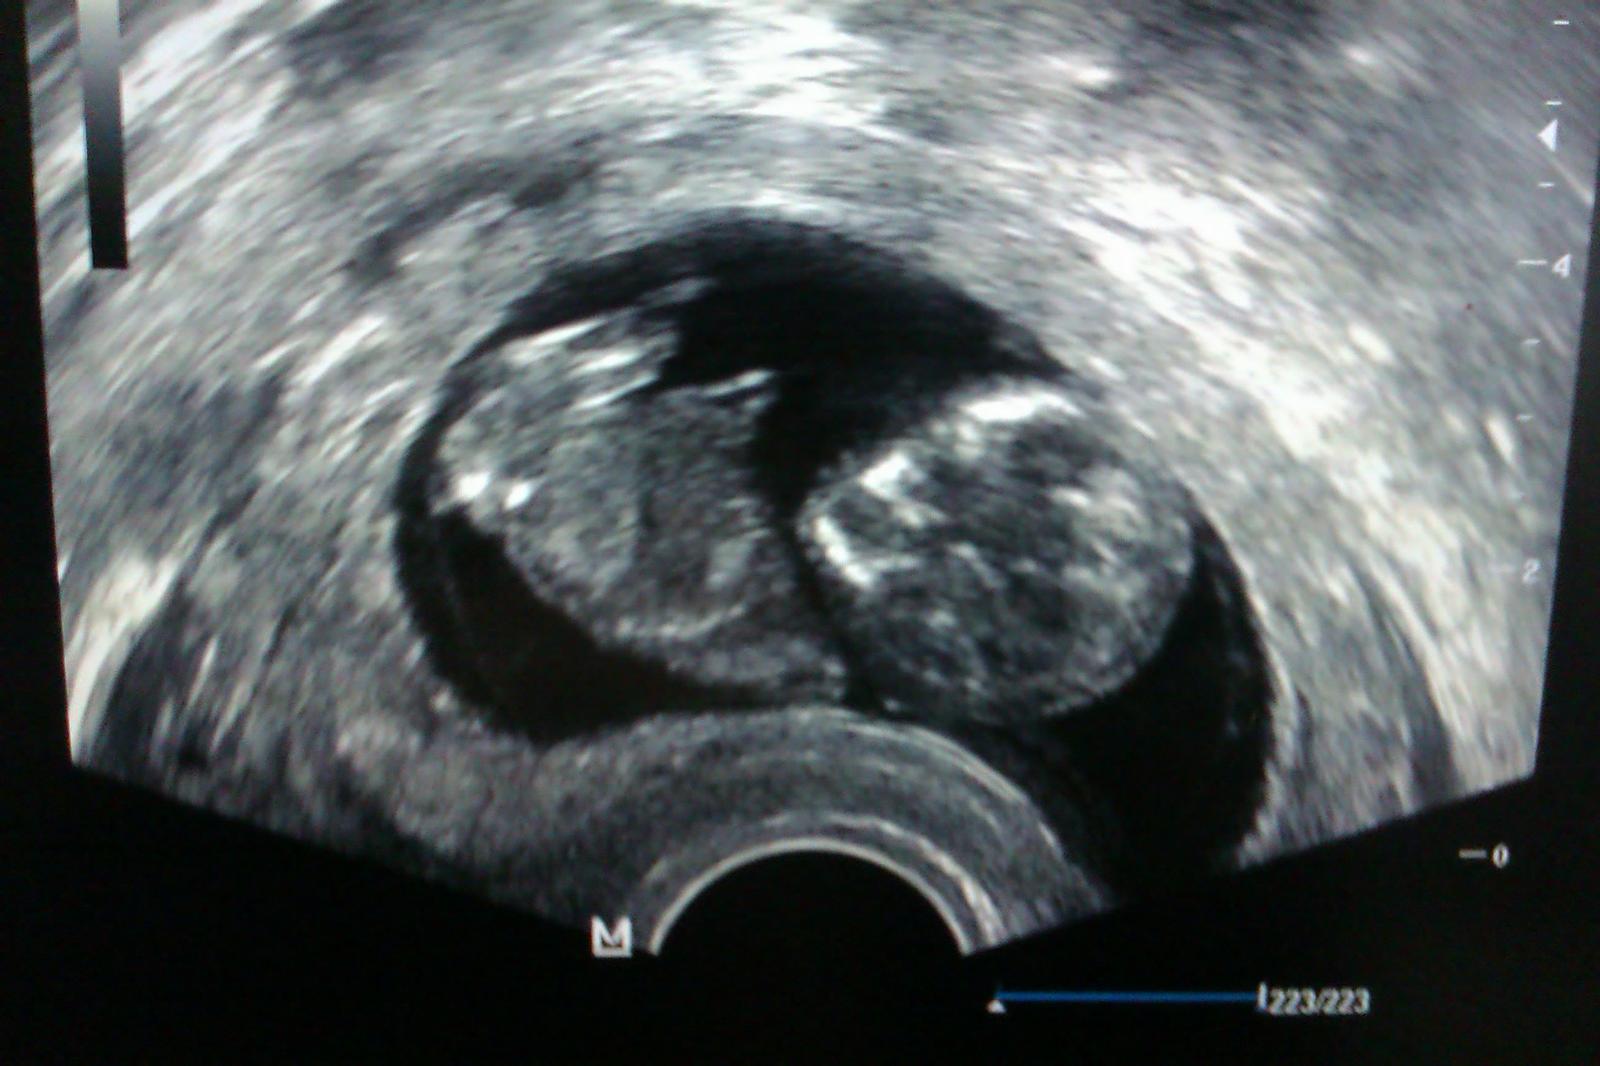

vcera sme boli kuknut babko na sone, si tancovalo jak keby nacvicovalo kreacie na silvestrovsku zabavu, asi nevie, ze budeme spat 🙂 uz ma 6,8cm a meranie NT dopadlo super, iba 1,1cm 😵 a uz aj bublinka ma krajsi tvar 😉